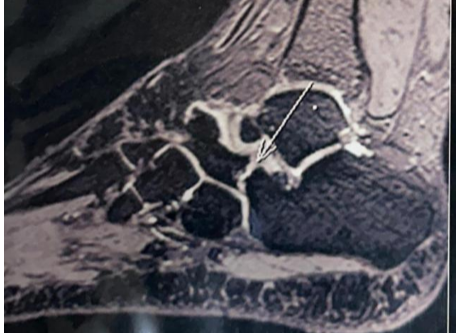

An 18-year-old female cricket athlete presented with a gradually increasing swelling and pain over the anterolateral aspect of the right ankle for 5 years. She had a history of a lipoma on the dorsum of the foot 5 years prior. Pain was aggravated during running and dorsiflexion, limiting sports activity. On examination, a soft, non-tender swelling was palpable over the anterolateral ankle with restriction of dorsiflexion, terminally with restricted hindfoot movements. On local examination, a soft, non-tender, well-defined swelling measuring approximately 6 × 3 cm was noted over the anterolateral aspect of the right ankle. The overlying skin was normal with no signs of inflammation. There was a terminal restriction of dorsiflexion as well as inversion–eversion. Distal neurovascular examination was normal. X-rays were taken for further evaluation, which showed calcaneonavicular coalition (Fig. 1).

Figure 1: Calcaneonavicular coalition.